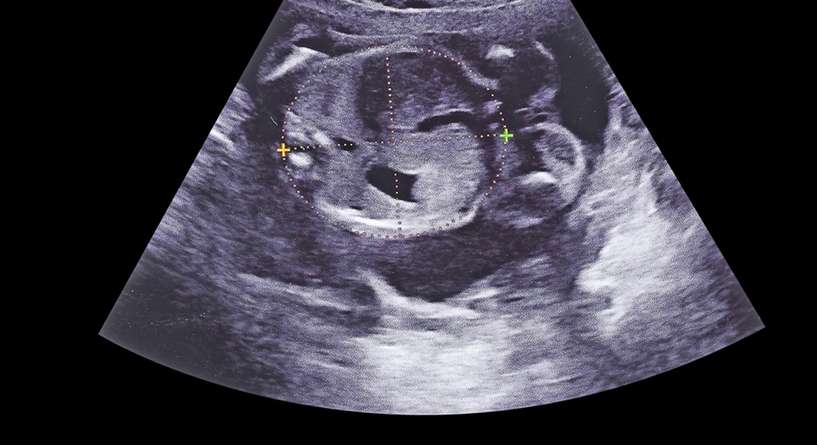

خلال كل مرحلة من مراحل الحمل، تطرحين على نفسك مختلف الأسئلة التي تدور حول حركة الجنين في بطنك. لا يمكن للمرأة أن تصف مدى سعادتها عندما تشعر بحركة الجنين إذ يشير هذا الأمر إلى أن مولودها المنتظر بخير وبصحة جيدة. لكن هل تعلمين اين تكون حركة الجنين في الشهر الخامس؟ هل تشعرين بحركته في المنطقة السفلية أو العلوية من البطن؟ تابعينا في هذا المقال من "عائلتي" إذ سنجيبك على كل هذه الأسئلة التي تخطر في بالك.

تشعر المرأة بحركة الجنين بدءًا من الشهر الرابع أو الخامس من الحمل. لذلك، في بعض الأحيان، قد تكون الركلة الأولى التى تشعرين بها هي خلال هذا الشهر تحديداّ. تشعرين بحركة خفيفة لتزداد قوتها مع تقدم الأيام.

أما بالنسبة للمنطقة التي يتحرك فيها الجنين، يشير البعض إلى أن حركة الولد تكون مرتكزة أكثر على الجزء العلوي من البطن وحركة الأنثى تكون في الجزء السفلي من البطن. لكن هذه المعلومات غير دقيقة وغير مؤكد منها حتى الآن.

السونار وتحديد جنس الجنين في الشهر الخامس

الأسبوع التاسع عشر هل السونار يخطئ في تحديد نوع الجنين في الشهر الخامس؟

تعرفي الى دور السونار في تحديد نوع الجنين في الشهر الخامس!